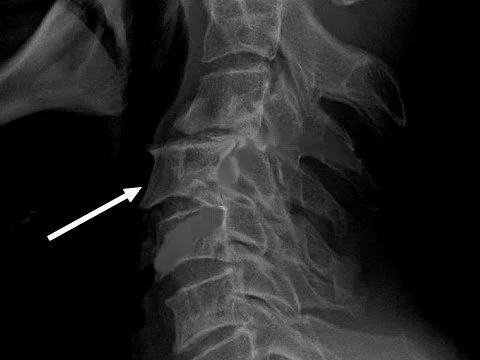

Как правило, антелистез развивается на фоне сопутствующих заболеваний опорно-двигательной системы, например, сколиоза или остеохондроза. Диагноз ставится на основании рентгенографического обследования, в редких случаях дополнительно требуется МРТ (магнитно-резонансная томография) или КТ (компьютерная томография).